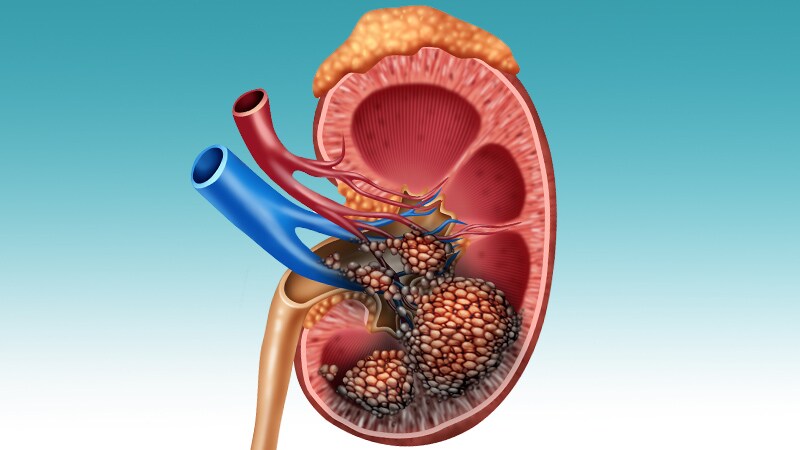

Testicular Cancer Deaths Rising Among Hispanic MenTesticular cancer–specific mortality rates in the United States have been increasing, particularly among Hispanic men and

in certain geographic locations.